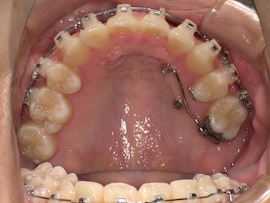

そして1ヶ月後、

牽引のため内側の装置が新しくなりましたが、これがびっくりするくらい話しづらいです…。

元々装置はついていたので案外大丈夫かと思っていたのですが、想像以上の違和感でした。

また、異物を感じているのか明らかに唾液の量が増えた気がします。(笑)

慣れるのかどうか本当に不安で先生にも「完全には慣れないかもしれない」と言われたものの、1週間くらいすれば気にならない程度には慣れました。口の中ってすごいですね。(笑)

準備ができたのでいよいよ数日後に開窓(歯茎を切って埋まっている歯にボタンをつけてもらうこと)を他院で行います。